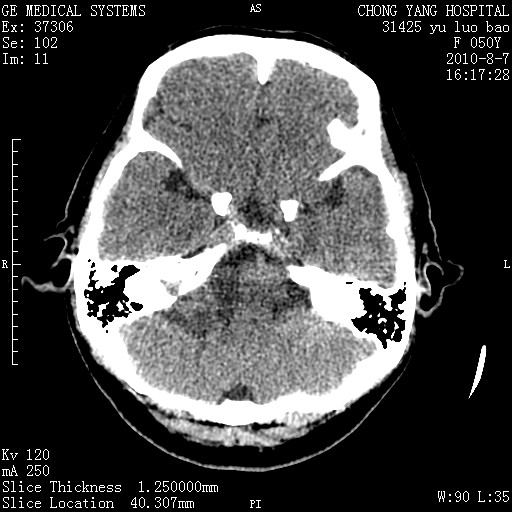

标题: CT28285:听力下降一年,头昏。

右侧桥小脑角区占位--听神经瘤,建议增强或mri检查。

右侧桥小脑角去等密度占位,右侧内听道扩大、骨质吸收,考虑:右侧听神经瘤,建议增强检查。

右侧内听道扩大、骨质吸收,中脑受压左移,考虑:右侧听神经瘤,建议增强检查。支持!

右侧桥小脑角区等密度占位,内耳道扩大,听神经瘤